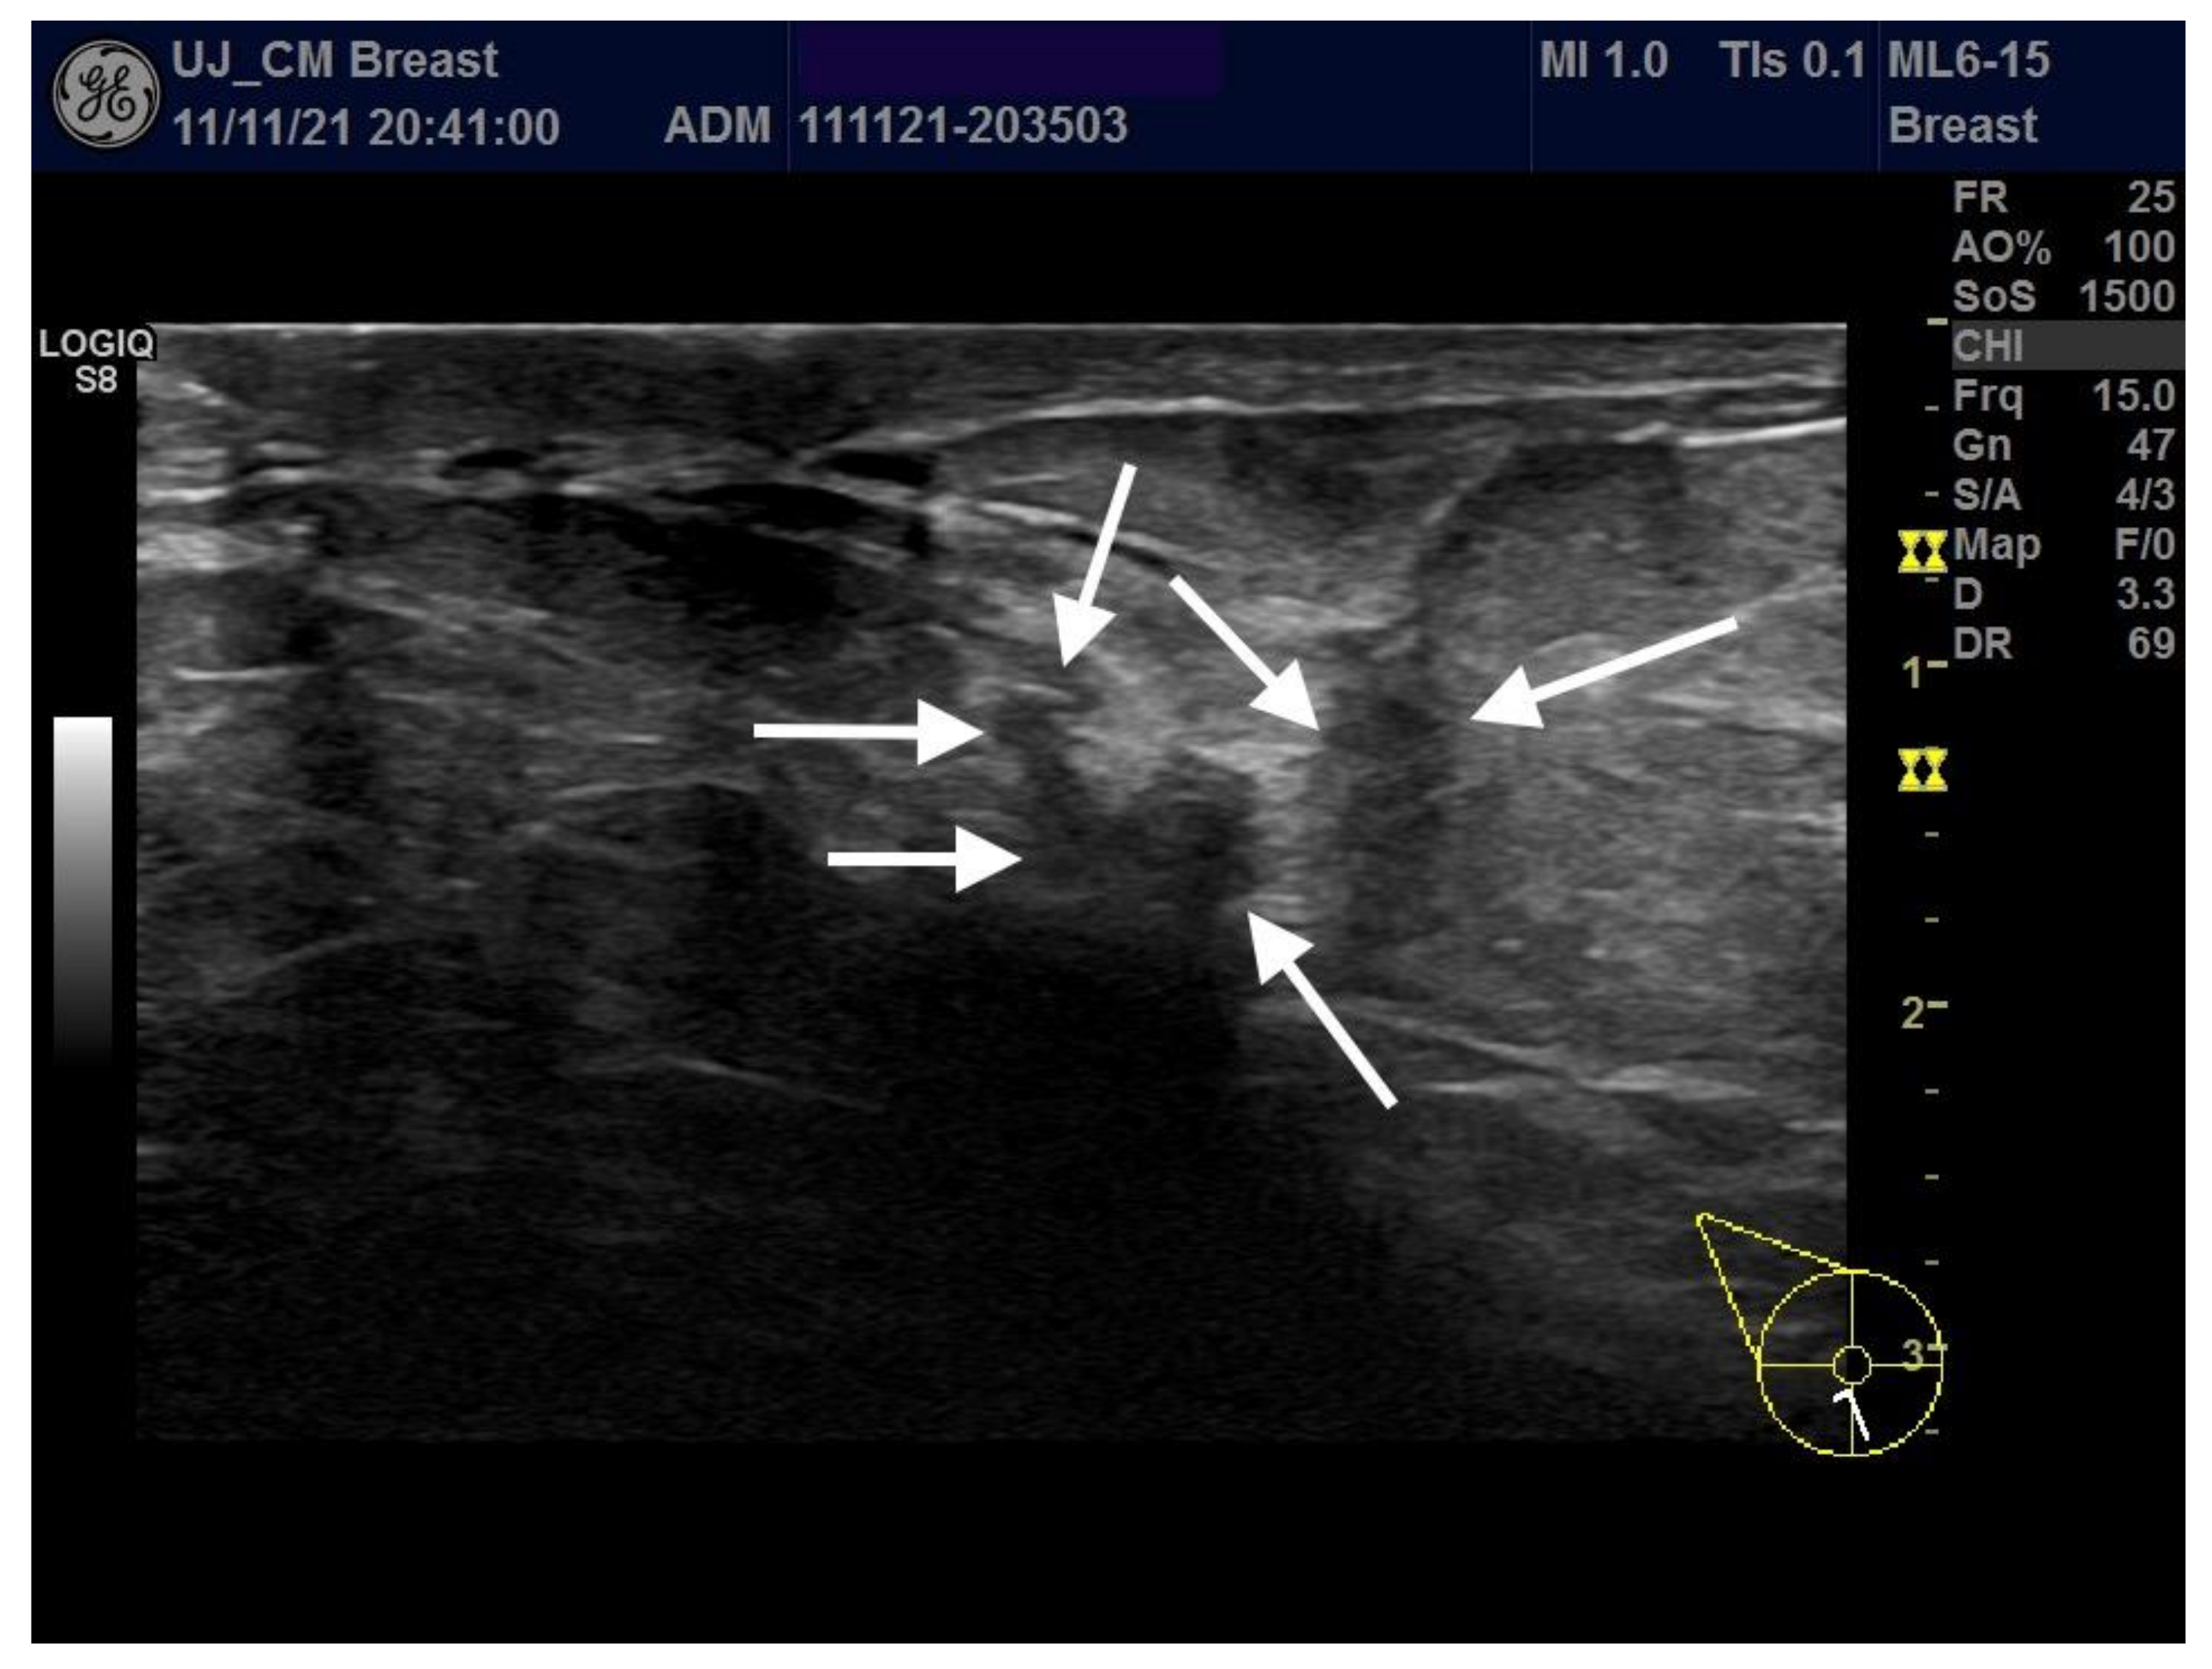

6. Imaging Findings